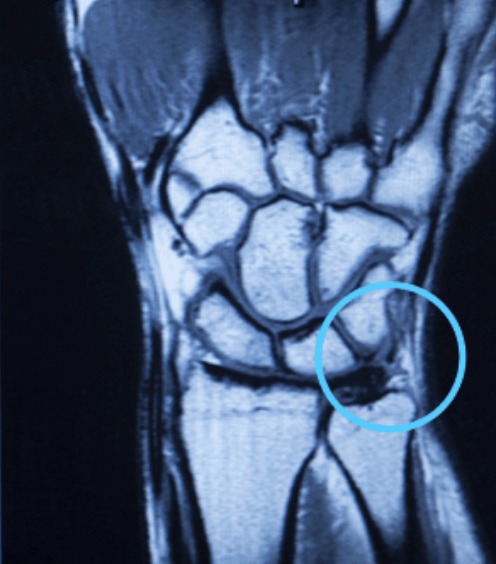

- MRI arthrogram: Gold standard — gadolinium contrast permeates through the tear, highlighting the defect. Sensitivity and specificity >85% in experienced hands.

- Wrist arthroscopy: The definitive diagnostic and therapeutic tool. Allows direct visualisation of the TFCC, assessment of the size and location of the tear, and simultaneous treatment.